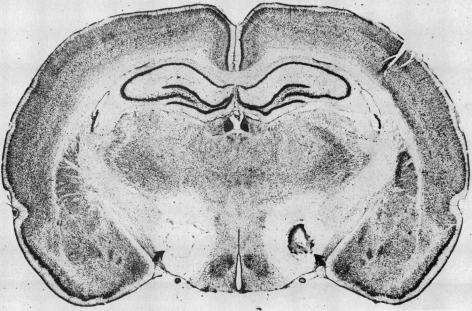

进食行为的启动和终止尚未完全明确。胃被认为是调节食物摄入信号的一个来源。食物的视觉和嗅觉是胃酸分泌和胃收缩的有力刺激因素。口腔、上消化道和肝脏含有调节食物摄入的受体;传入信息传入脑干和脑区。下丘脑外侧损伤会导致进食停止、体温升高、基础胃酸分泌增加,并产生胃糜烂。迷走神经切断术和给予溴丙胺太林可消除此类损伤后胃酸分泌的增加;它们还会改变黏膜屏障,使质子扩散到黏膜细胞中。几种神经肽通过中枢神经系统,通过调节自主神经系统来刺激或抑制胃酸分泌。大多数胃糜烂的动物模型都与体温降低有关。尚不清楚这种关联是否是促甲状腺激素释放激素水平升高的结果,当脑池内注射促甲状腺激素释放激素时,它是胃酸分泌和糜烂形成的有力刺激因素。

https://cdn.ncbi.nlm.nih.gov/pmc/blobs/d394/1306273/724722596a9c/westjmed00168-0073-a.jpg